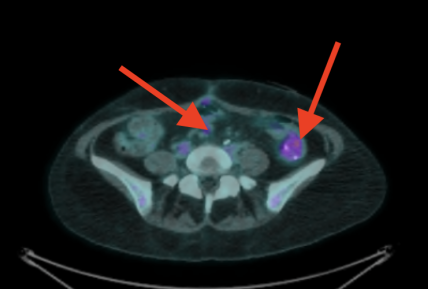

I've had 3 scans. First scan it was 3cm with a SUV max score of 5 point something. (For my type of cancer, 2.5 or above is considered cancerous... it's how much of the radioactive stuff is detected in the spot. Or something like that.) My second scan it was about 1 cm with a SUV max score of I think 2.6. Then this last scan it was still 1 cm but the SUV max score was 1.9. I'd have to log back in to confirm those numbers but that's what I recall.

February: 3 cm:

June: 1 cm with inflammation at the staple line of my Hartmann's pouch:

September: Inflammation resolved, spot still 1 cm (but no FDG uptake):

Previously depicted left retroperitoneal nodal mass in the common iliac station measures 0.9 cm in short axis, unchanged (SUV max 1.9, previously 2.6, image 224). Elsewhere below the diaphragm, tracer activity is unremarkable. Calcified mass closely associated with bowel in the left hemiabdomen is unchanged. Left renal cyst. There are postoperative changes of the colon with left lower quadrant ostomy. There are no FDG avid skeletal lesions.

No findings convincing for FDG avid malignancy. The left common iliac nodal lesion is not FDG avid and is similar in size to the prior study.